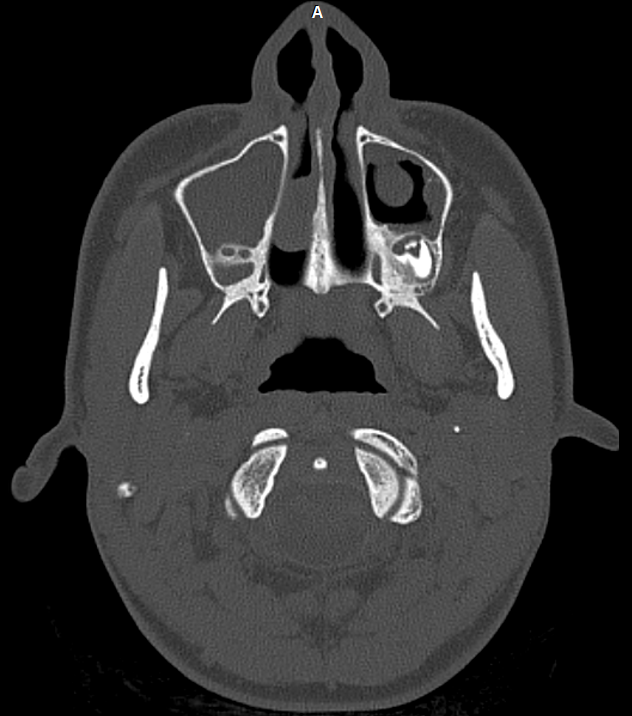

КТ-снимки хронического этмоидита: подробная визуализация